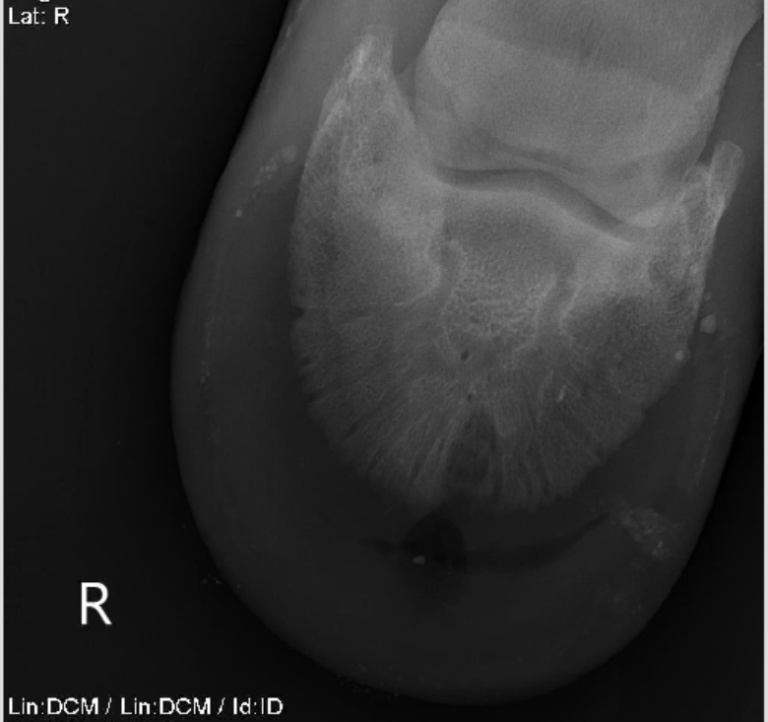

Horse Hoof Keratoma . They develop slowly over time and may go unnoticed until they reach a size that interferes with the horse’s soundness. Cylindrical keratomas look like columns. Gray calls on the expertise of the smartpak hoof health consultant danvers child to describe the appearance and typical shape of keratomas, talk about why they can be. A keratoma is a benign tumor of the hoof that grows inside the horse's foot. A keratoma is a rare, benign tumour that is found within the foot. It consists of abnormal masses of keratin (the main. Keratomas in horses are abnormal growths or benign tumors that develop within the hoof capsule, potentially resulting in lameness and discomfort. In horses, a keratoma is a benign epithelial tumor of the hoof capsule. They should be suspected whenever a horse is suffering from a. Keratoma of the hoof is a uncommon cause of persistent lameness in the horse.

Keratoma of the hoof is a uncommon cause of persistent lameness in the horse. A keratoma is a rare, benign tumour that is found within the foot. They develop slowly over time and may go unnoticed until they reach a size that interferes with the horse’s soundness. They should be suspected whenever a horse is suffering from a. A keratoma is a benign tumor of the hoof that grows inside the horse's foot. Gray calls on the expertise of the smartpak hoof health consultant danvers child to describe the appearance and typical shape of keratomas, talk about why they can be. It consists of abnormal masses of keratin (the main. In horses, a keratoma is a benign epithelial tumor of the hoof capsule. Cylindrical keratomas look like columns. Keratomas in horses are abnormal growths or benign tumors that develop within the hoof capsule, potentially resulting in lameness and discomfort.

Horse Hoof Keratoma A keratoma is a benign tumor of the hoof that grows inside the horse's foot. A keratoma is a rare, benign tumour that is found within the foot. They should be suspected whenever a horse is suffering from a. They develop slowly over time and may go unnoticed until they reach a size that interferes with the horse’s soundness. It consists of abnormal masses of keratin (the main. A keratoma is a benign tumor of the hoof that grows inside the horse's foot. Gray calls on the expertise of the smartpak hoof health consultant danvers child to describe the appearance and typical shape of keratomas, talk about why they can be. Cylindrical keratomas look like columns. Keratoma of the hoof is a uncommon cause of persistent lameness in the horse. Keratomas in horses are abnormal growths or benign tumors that develop within the hoof capsule, potentially resulting in lameness and discomfort. In horses, a keratoma is a benign epithelial tumor of the hoof capsule.